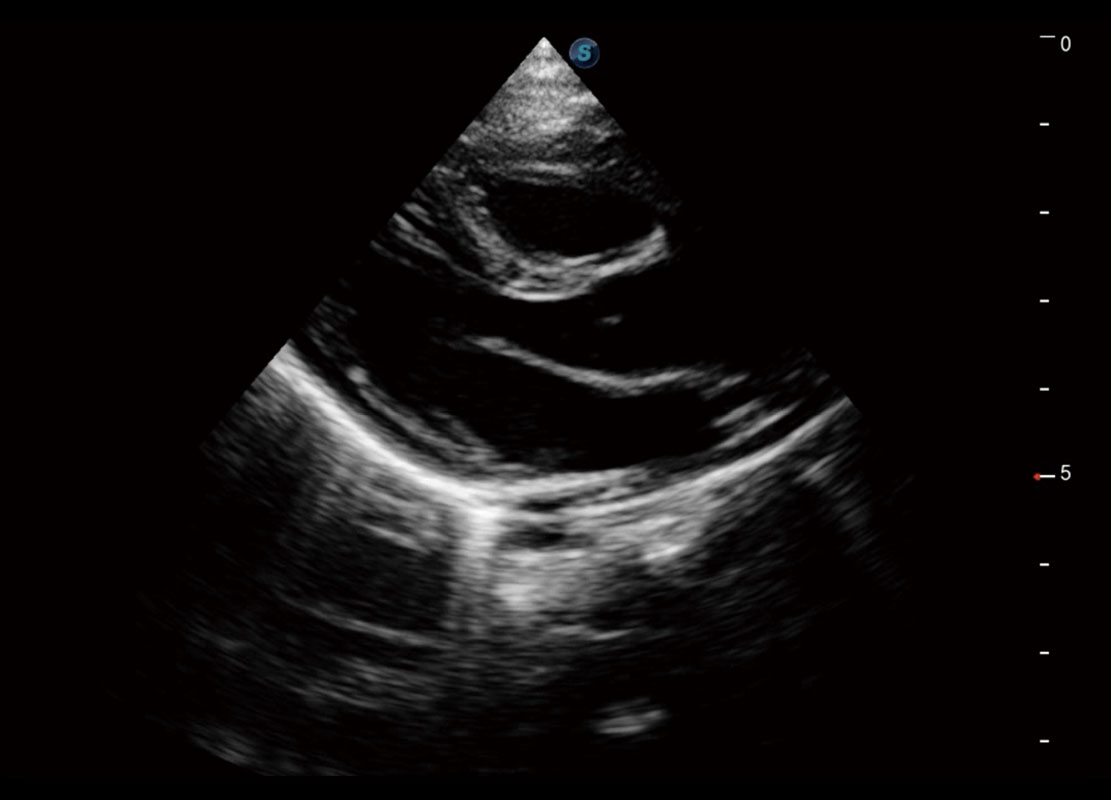

P60搭載一系列胎兒心臟成像技術(shù),實現(xiàn)精細的胎兒心臟評估。

四腔切面